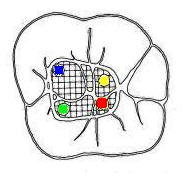

Primer Molar Inferior

Esta pieza dentaria es la más voluminosa de la arcada. Posee por general dos raíces bien definidas una mesial y otra distal, ambas aplanadas en sentido mesiodistal. La raíz mesial presenta una curvatura acentuada, mientras que la distal puede ser algo curva o recta.

Cuando tiene tres conductos el mas amplio es el distal con una sección oval y su curvatura es suave o recta. Si presenta cuatro conductos la raíz distal contendrá dos de ellos y son de diámetro más pequeño y en caso de presentar dos conductos, ambos son amplios.